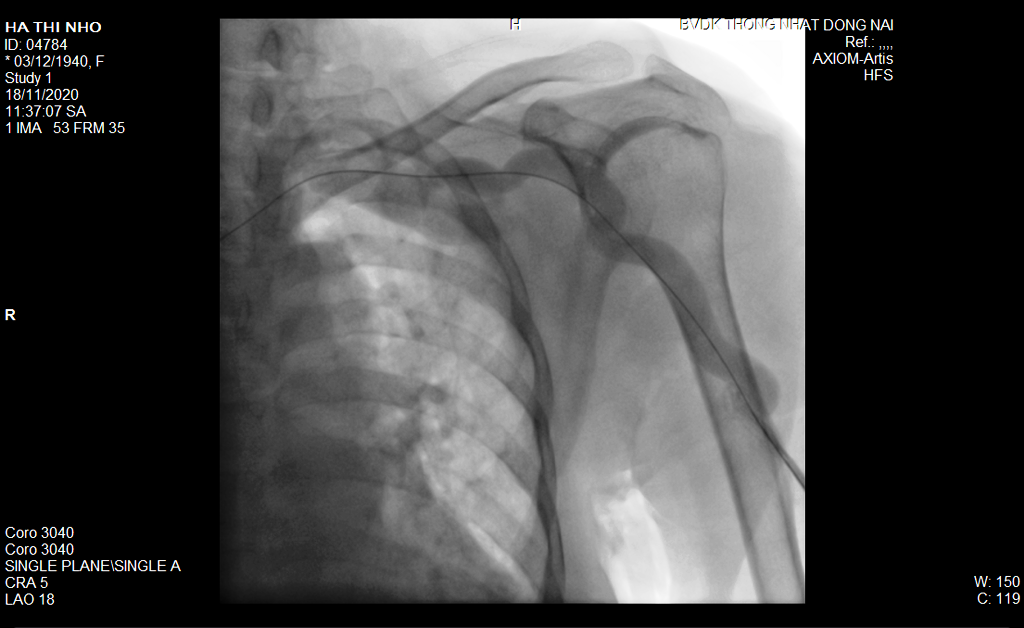

5.1 Chụp và can thiệp động mạch vành qua da:

Nong bóng, khoan cắt mảng xơ vữa, đặt stent giúp giải quyết các tổn thương hẹp, tắc động mạch vành gây nhồi máu cơ tim, đau thắt ngực không ổn định, đau thắt ngực ổn định không đáp ứng với điều trị nội khoa tối ưu

Một trường hợp chụp và can thiệp tổn thương ĐMV phức tạp với hệ thống DSA Siemens Artis Zee có siêu âm trong lòng mạch vành Volcano hỗ trợ